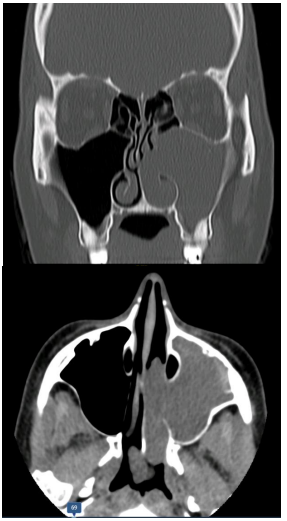

Mulher, 43 anos de idade, refere rinorreia purulenta, obstrução

nasal e cefaleia há mais de um ano, apenas em fossa nasal

direita. Ao exame físico, evidencia-se pólipos nasais e

secreção purulenta em meato médio a direita, mas sem

alterações no lado esquerdo. Foi realizada tomografia da face,

conforme imagens a seguir:

Qual achado de exame adicional você esperaria para o quadro?